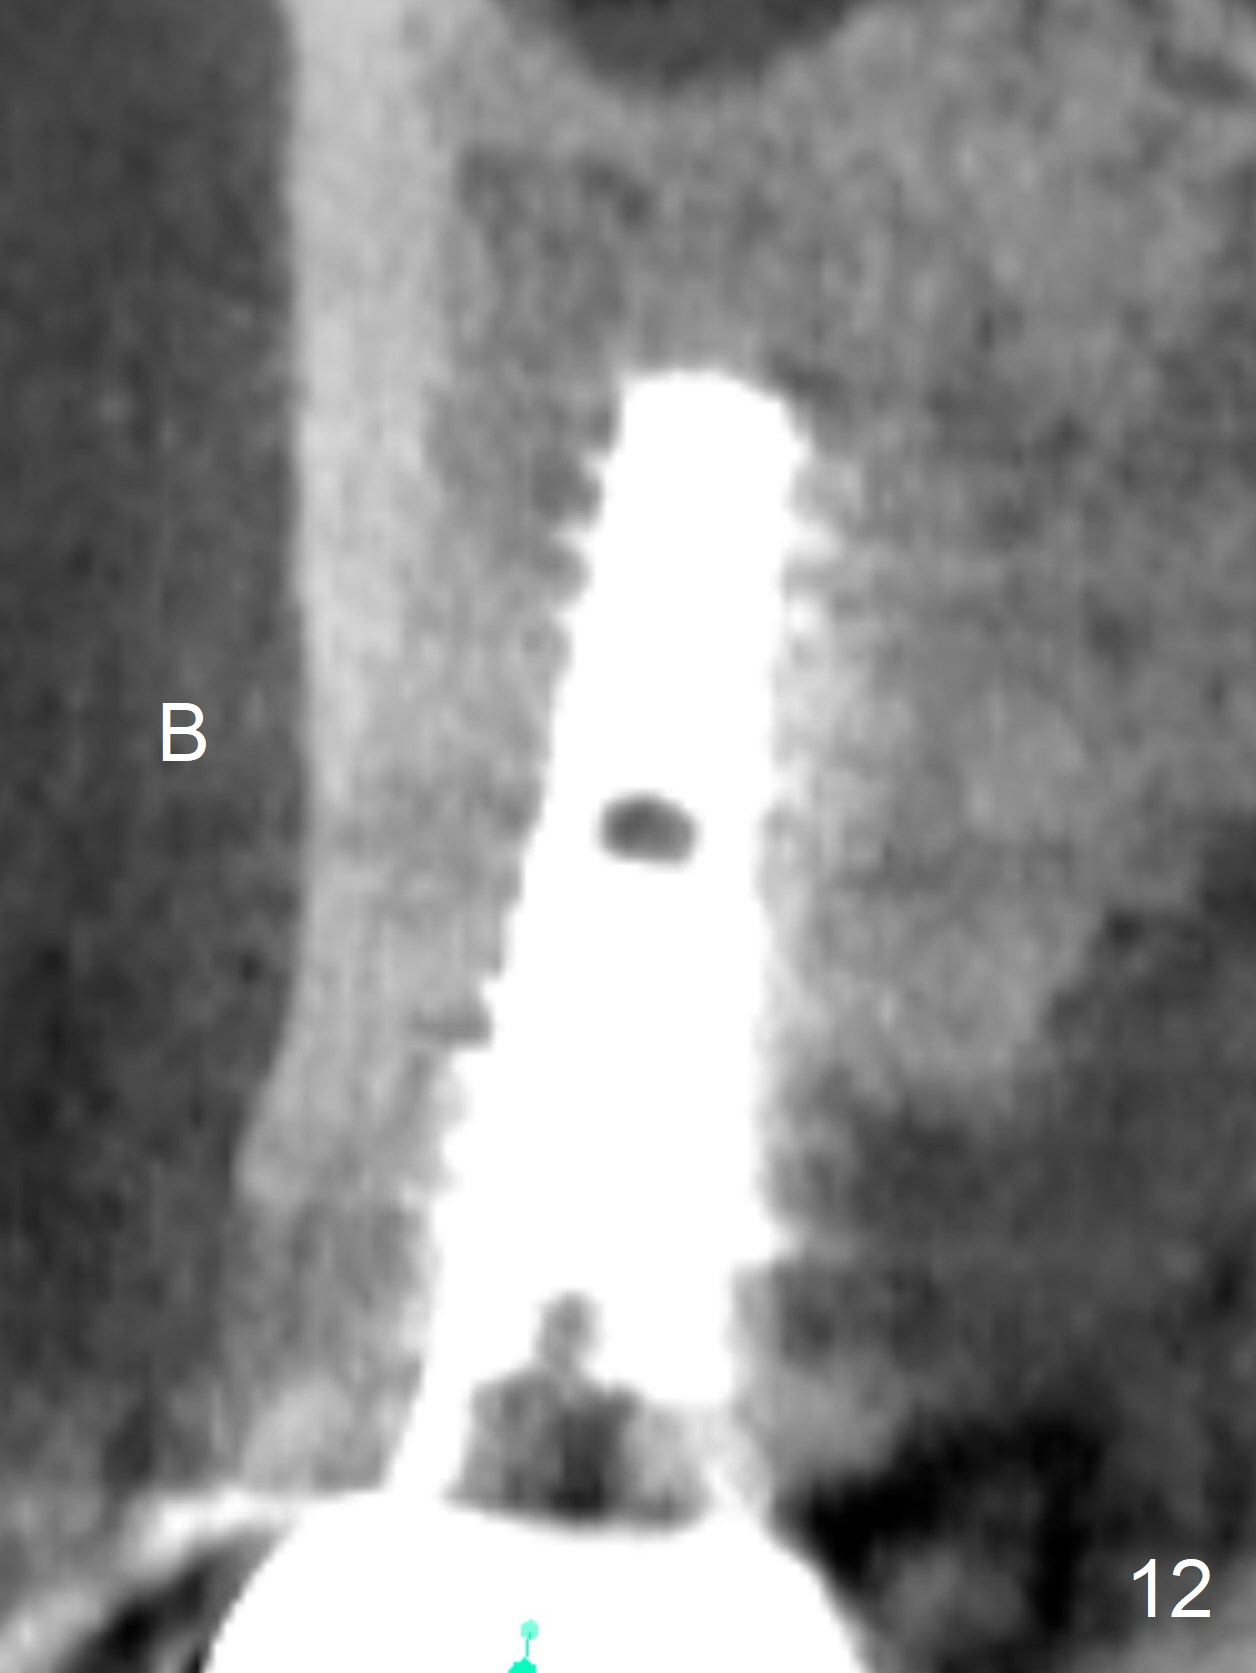

The distal papilla reforms buccally (Fig.8 *) and palatally (Fig.9) 4 months postop. It appears that the 4 mm cuff of the pair abutment (Fig.10 >) is apical to the mesial crest (*). The distal coronal implant threads seem to be covered by bone graft (Fig.11 <). Therefore pair abutments with 5 mm or more cuff are required in cases of the uneven bone. Implants have to be placed deep. CT taken 3 months post cementation (10 months postop) shows that the implant is placed in the middle of the alveolus without apparent thread exposure. CT taken 1 year and 8 months post cementation (Fig.13) shows that the implant is placed in the middle of the alveolus without apparent thread exposure, as compared to those at #2 and 3, which are placed buccal (B).